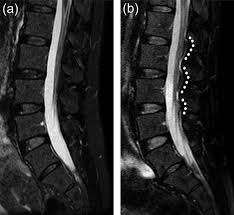

This first pic is from the internet – basically it means that fluid is collecting along my spine that looks like those raised white dots in the pic on the right (b).

This pic is my spine, and yep, there are those raised white bumps. Seems like they could come up with a better name than dinosaur tail, but here we are.